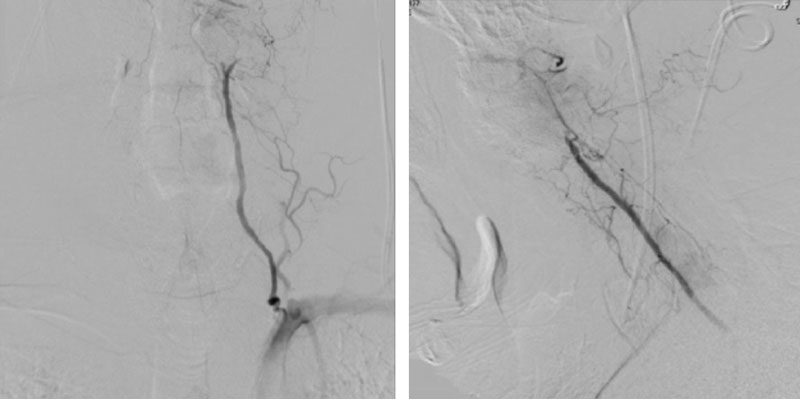

On rotation to the left, the patient experienced mild symptoms, however no significant Vertebral Artery or basilar reduction in flow was observed. On rotation to the right, the patient experiences slightly more moderate symptoms, however no significant Vertebral Artery or vascular reduction flow was observed. On hyper extension of approximately 10-15 degrees, passively performed by the patient until symptoms are reproduced, angiogram demonstrates complete occlusion of the right Vertebral Artery at approximately the C2-C1 level. (Figure 5)